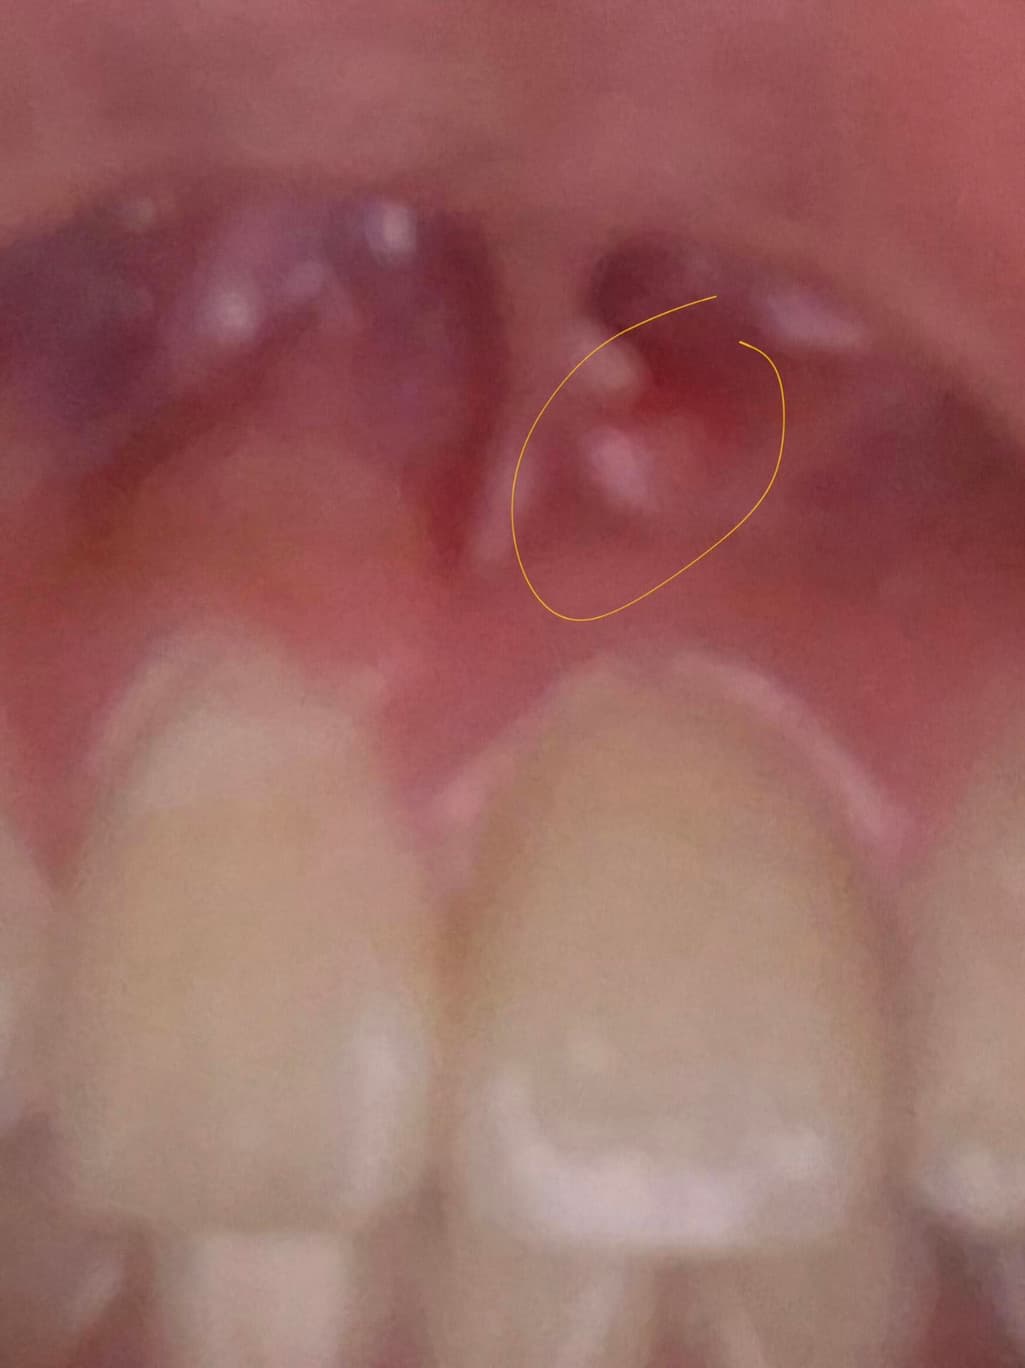

잇몸에 이물감이 느껴져서 다녀왔는데 이게 뭘까요?

사진으로 봤을 경우 근단주위 치주염일 가능성이 있습니다. 신경관에 감염이 되면 염증이 치조골 밖으로 나오게 되면서 생기는 증상입니다.

정확한 확인을 위해서는 방사선 사진이 필요하기 때문에 자세한 확인을 위해서 치과에서 진료를 받아보는 것을 권유드립니다.

잇몸에 무엇이 난 것이 맞다면 염증일 수도 있지만 치과에서 문제 없다했으면 침샘 일수도 있습니다.

사진에 보이는 부분에서 계속 여드름 처럼 염증이 생기면 치아 뿌리끝에 염증이 잇어서 그럴수도 있습니다.

사진 초점이 맞지 않아 정확히 보이진 않으나 gingiva epulis 의 가능성이 있어보입니다 국소적으로 잇몸을 자극하는 자극원이 무엇인지 찾아봐야할 것 같습니다.